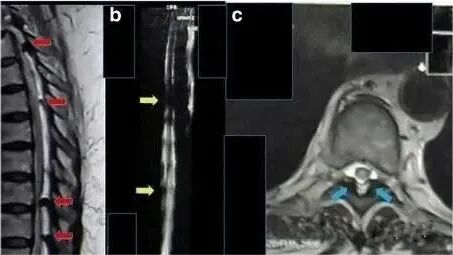

2017年海外报道一例62岁的印尼籍妇女,被诊断为胸部截瘫、慢性肾功能衰竭、糖尿病,长期肾脏受累,慢性肾功能衰竭2年,肌酐水平为11mg/dL,无小便。采用间充质干细胞治疗方案治疗。靶向注射1.6×10^7个间充质干细胞,静脉注射1.6×10^7个间充质干细胞。靶向注射和静脉回输后三周后,患者可以移动脚趾,肾功能得到改善。肌酐水平降至9 mg/dL。8个月后,患者可以抬起腿,肌酐水平是2mg/dL,小便恢复正常。由此可见,对于病变较重、病情常反复的患者,干细胞无疑是一种新的有效治疗手段,不仅能控制病情活动,还可以达到治愈的效果,对患者的病情带来极大的缓解改善。